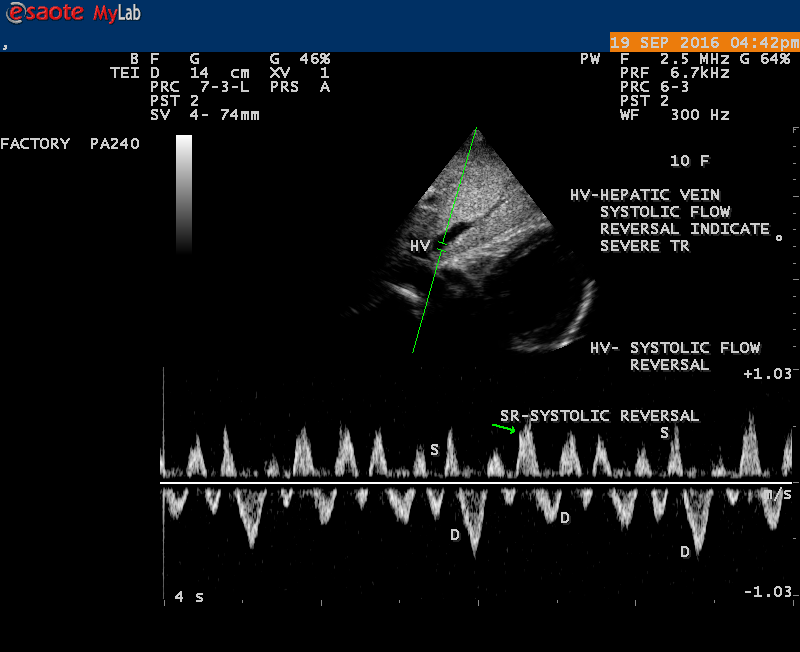

The severity of eccentric MR is underestimated because of coanda effect. If the regurgitant jet area fills < 20> 40% indicate severe regurgitation. The vena contracta ( the neck or narrowest portion of the jet), typically imaged perpendicular to the commissural line in parasternal long axis and apical four chamber views is well defined in both central and eccentric jets, but not in chaotic, disorganized jets due to flail leaflets. Its width < 3> 7 mm defines severe MR and a mean value of > 8mm indicates severe functional MR. The flow convergence method based on PISA (proximal isovelocity surface area) may not applicant for eccentric and multiple jets or complex and elliptical regurgitant orifices to assess the severity of mitral regurgitation.. The adaptation of LV to the increased volume overload is reflected by LV dimensions and ejection fraction.. In chronic compensated phase, the forward stoke volume is maintained through an increase in LV ejection fraction >65% and the patient could be asymptomatic. In chronic decompensated phase of MR, the forward stroke volume decreases and the LA pressure increase significantly. The patient may be still asymptomatic and the LV ejection fraction may be in the low normal range despite the presence of significant muscle dysfunction. The contractile function decreases silently and become irreversible. In the current guidelines, surgery is recommended in asymptomatic patients with severe organic MR when the LV ejection fraction is ≤ 60%. However, in acute stage, the LV ejection fraction increases in response to the increased preload. The end-systolic diameter is less preload dependent than the ejection fraction and it may be more appropriate to monitor the global LV function. The end-systolic diameter > 45 mm also indicate the need for mitral valve surgery [43]. In this child, the LVESD (end-systolic diameter) is 30.7 mm and the ejection fraction (EF) is 66% as shown in Figure 19. New parameters are currently available for a better assessment of LV function. A systolic tissue Doppler velocity measured at the lateral annulus <10>40-50mm) may predict the onset of atrial fibrillation and poor prognosis in patients with organic MR[48]. The excess regurgitant blood entering in the LA may induce acutely or chronically a progressive rise in pulmonary pressure and the presence of TR (tricuspid regurgitation) as shown in Figures 26 and 28 permits the estimate of systolic pulmonary arterial pressure and mitral valve surgery is recommended when it is > 50 mmHg at rest and LA reverse remodeling may occur after surgery. The severe TR may cause a decrease in hepatic vein systolic velocity and systolic flow reversal may occur as shown in Figure 32 and its sensitivity is 80% [49]. The TR (tricuspid regurgitation) jet velocity in this child is 4.03 m/s as shown in Figure 28 which corresponds to a systolic pulmonary artery pressure of 65 mmHg.